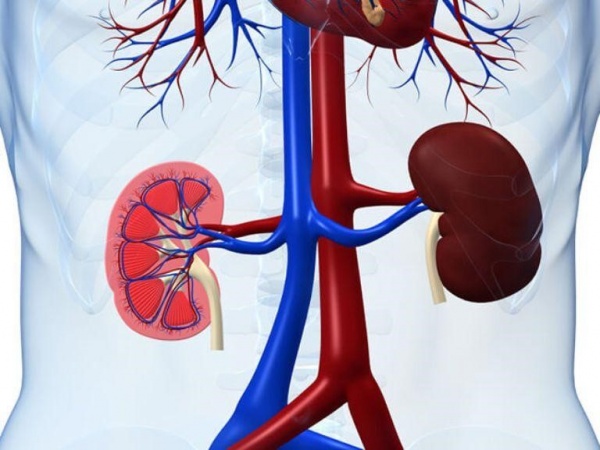

Текущая пандемия COVID-19 характеризуется в основном тяжелым острым респираторным синдромом со стороны легких, но также отмечаются нарушения функций других органов, включая сердце и кровеносные сосуды.